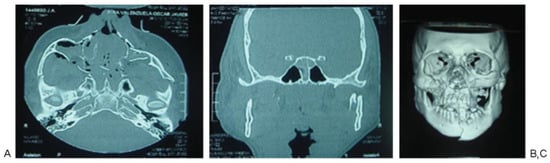

Figure 2. Patient 1: high-energy trauma and panfacial fractures. (A) Zygomatic arch, malar, and upper jaw fractures. (B) Sphenoid sinus fracture. (C) Computed tomography three-dimensional reconstruction showing the fractures at the middle third and jaw.

According to Manson’s classification, 17.9% (n ¼ 38) of the trauma in the group corresponded to high-energy trauma, followed by medium-energy trauma at 33.5% (n ¼ 71) and low-energy trauma at 48.6% (n ¼ 103). Among the patients with high-energy trauma, 31.5% (n ¼ 12) had combined fractures of the sphenoid bone and sphenoid sinus and 31.5% (n ¼ 12) had sphenoid sinus fractures only. In contrast, 1.4% (n ¼ 3) of patients with middle-energy trauma had sphenoid bone fractures, 5.6% (n ¼ 4) of the patients had sphenoid sinus fractures, and 4.2% (n ¼ 3) of the patients had sphenoid bone and sphenoid sinus fractures. In the low-energy trauma group, only 1 patient presented sphenoid sinus fracture (0.97%; Table 3; Figure 2, Figure 3 and Figure 4).